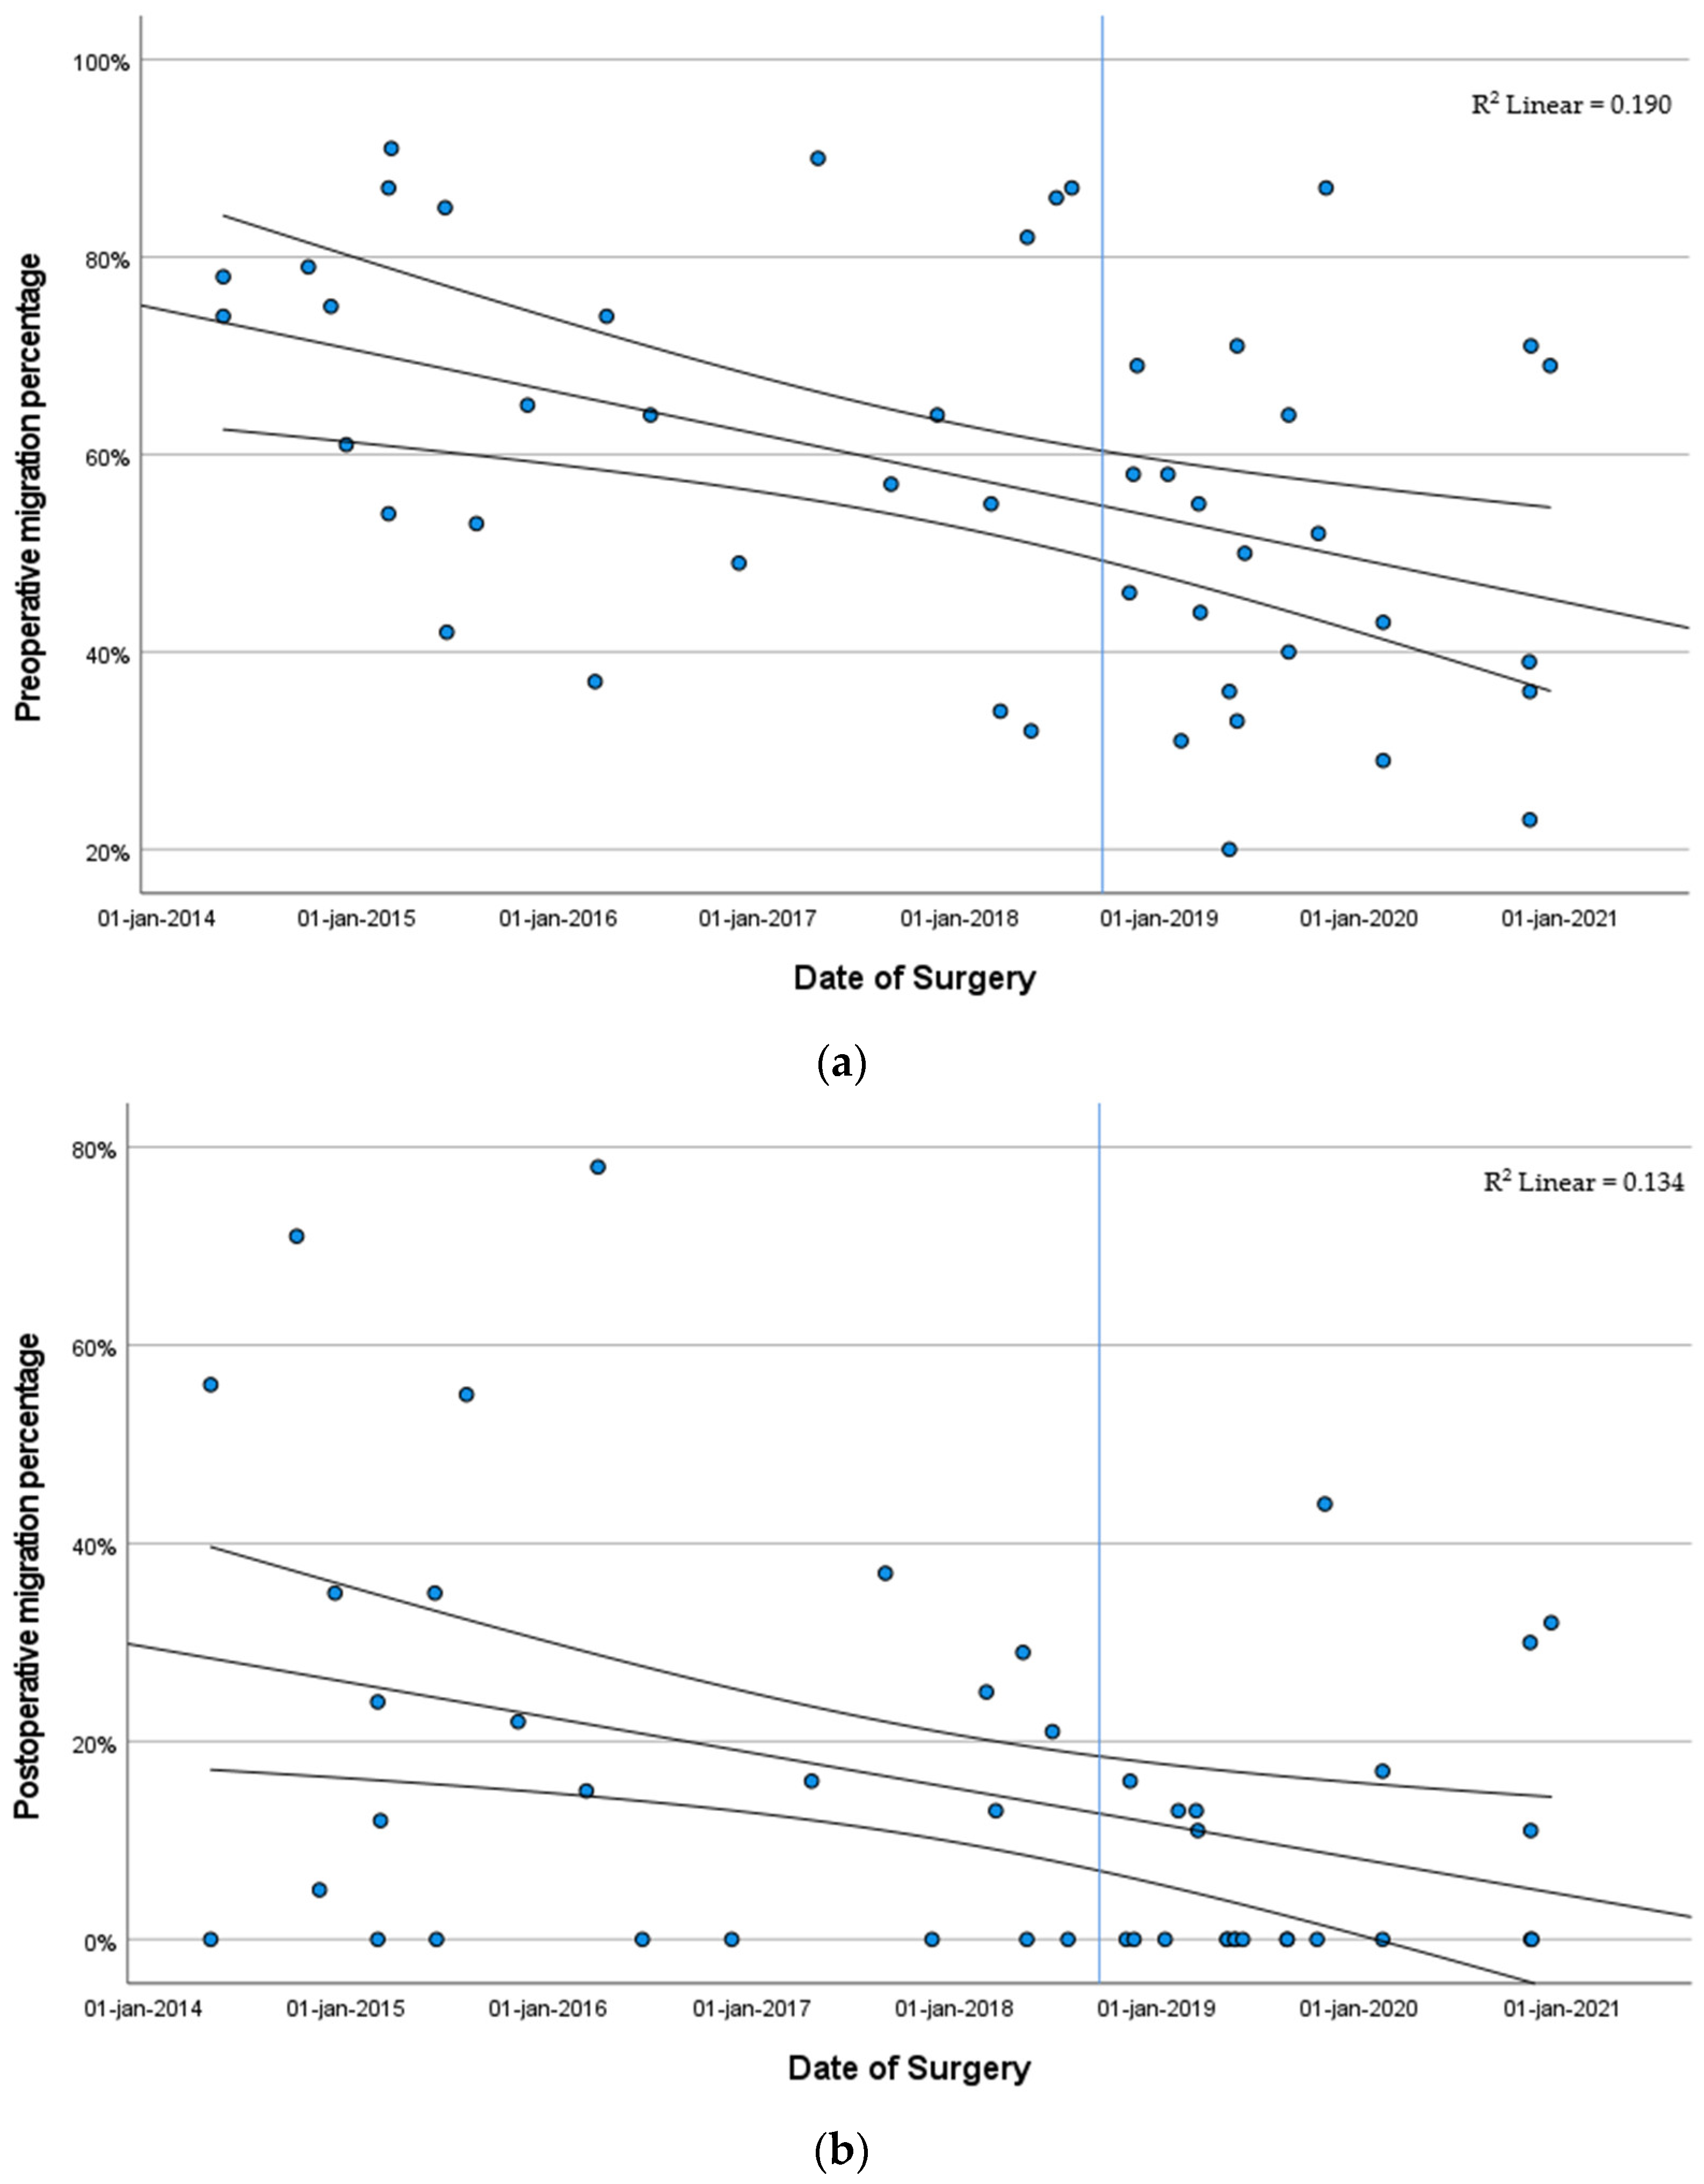

3.3. Hip Development

3.3.2. Migration Percentage Stratified by Year of Surgery

4. Discussion

5. Conclusions